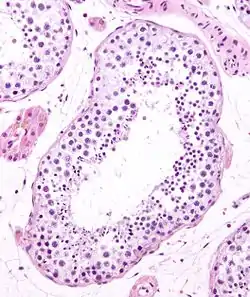

![]() Seminiferous tubule in cross-section (large tubular structure – center of image) with sperm (black, tiny, ovoid bodies furthest from the outer edge of the tubular structure). H&E stain. | |

Seminiferous tubules are located within the testicles, and are the specific location of meiosis, and the subsequent creation of male gametes, namely spermatozoa.

The epithelium of the tubule consists of a type of sustentacular cells known as Sertoli cells, which are tall, columnar type cells that line the tubule.

In between the Sertoli cells are spermatogenic cells, which differentiate through meiosis to sperm cells. Sertoli cells function to nourish the developing sperm cells. They secrete androgen-binding protein, a binding protein which increases the concentration of testosterone.